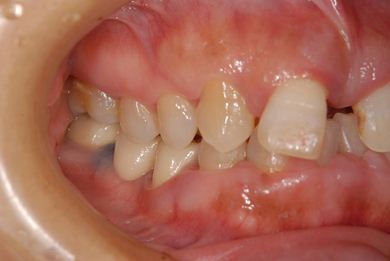

| 性別/年齢 | 女性 / 52歳 | ||||||||||||||||||||||||||||||||

| 主訴 | 歯周病で歯の位置がずれてしまった。 | ||||||||||||||||||||||||||||||||

| 治療内容 | インプラント2本(抜歯即日スピードインプラント)、メタルボンドセラミッククラウン4本 | ||||||||||||||||||||||||||||||||